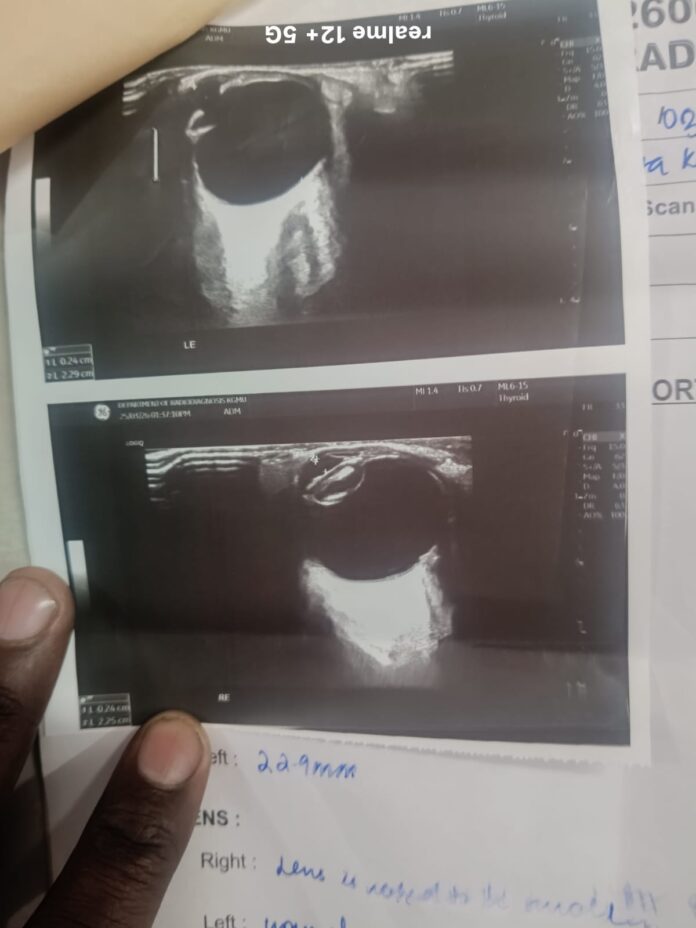

काकोरी क्षेत्र के जेहटा निवासी 57 वर्षीय गीता कश्यप को दाहिनी आंख में मोतियाबिंद की शिकायत थी। उनके पति गणेश प्रसाद कश्यप के अनुसार, 20 मार्च को केजीएमयू के नेत्र रोग विभाग में जांच कराई गई, लेकिन रिपोर्ट में बाईं आंख में खून के धब्बे का उल्लेख कर दिया गया। जबकि मरीज को समस्या दाहिनी आंख में थी।

जब यह रिपोर्ट बलरामपुर अस्पताल में दिखाई गई, तो वहां डॉक्टरों ने बाईं आंख को सामान्य बताया। इसके बावजूद केजीएमयू में ऑपरेशन की तैयारी शुरू कर दी गई और डॉक्टरों ने कथित रूप से कहा कि रिपोर्ट पर ध्यान न दें, ऑपरेशन सही आंख का होगा।